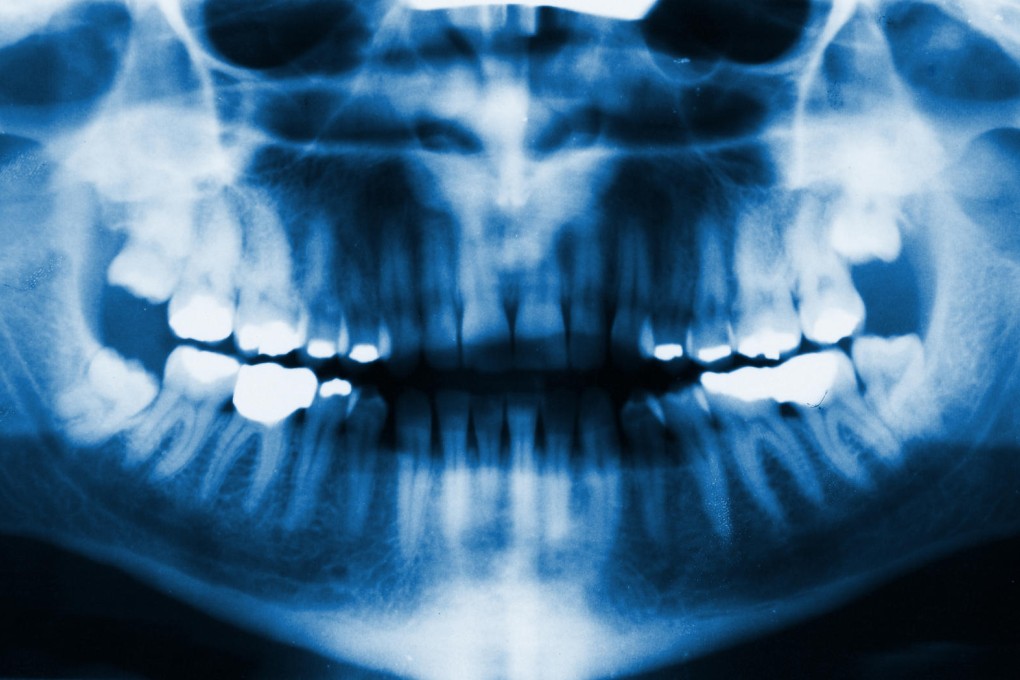

The researchers used a low-power laser to coax dental stem cells to form dentin, the hard tissue similar to bone that makes up most of a tooth, demonstrating the process in studies involving rats and mice and using human cells in a laboratory.

They did not regenerate an entire tooth because the enamel part was too tricky, but getting dentin to grow could end root canal treatment, the painful procedure to remove dead or dying nerve tissue and bacteria from inside a tooth, they said.